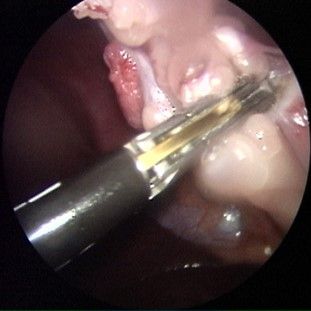

Orthopädische, Knochen-, Gelenks-Chirurgie

Orthopädische, Knochen- &

Gelenks-Chirurgie

Auch bei Kreuzbandrissen, Knorpeldefekten sowie bei Frakturbeandlungen bieten wir die passenden Opeartions- und Behandlungsmethoden an.